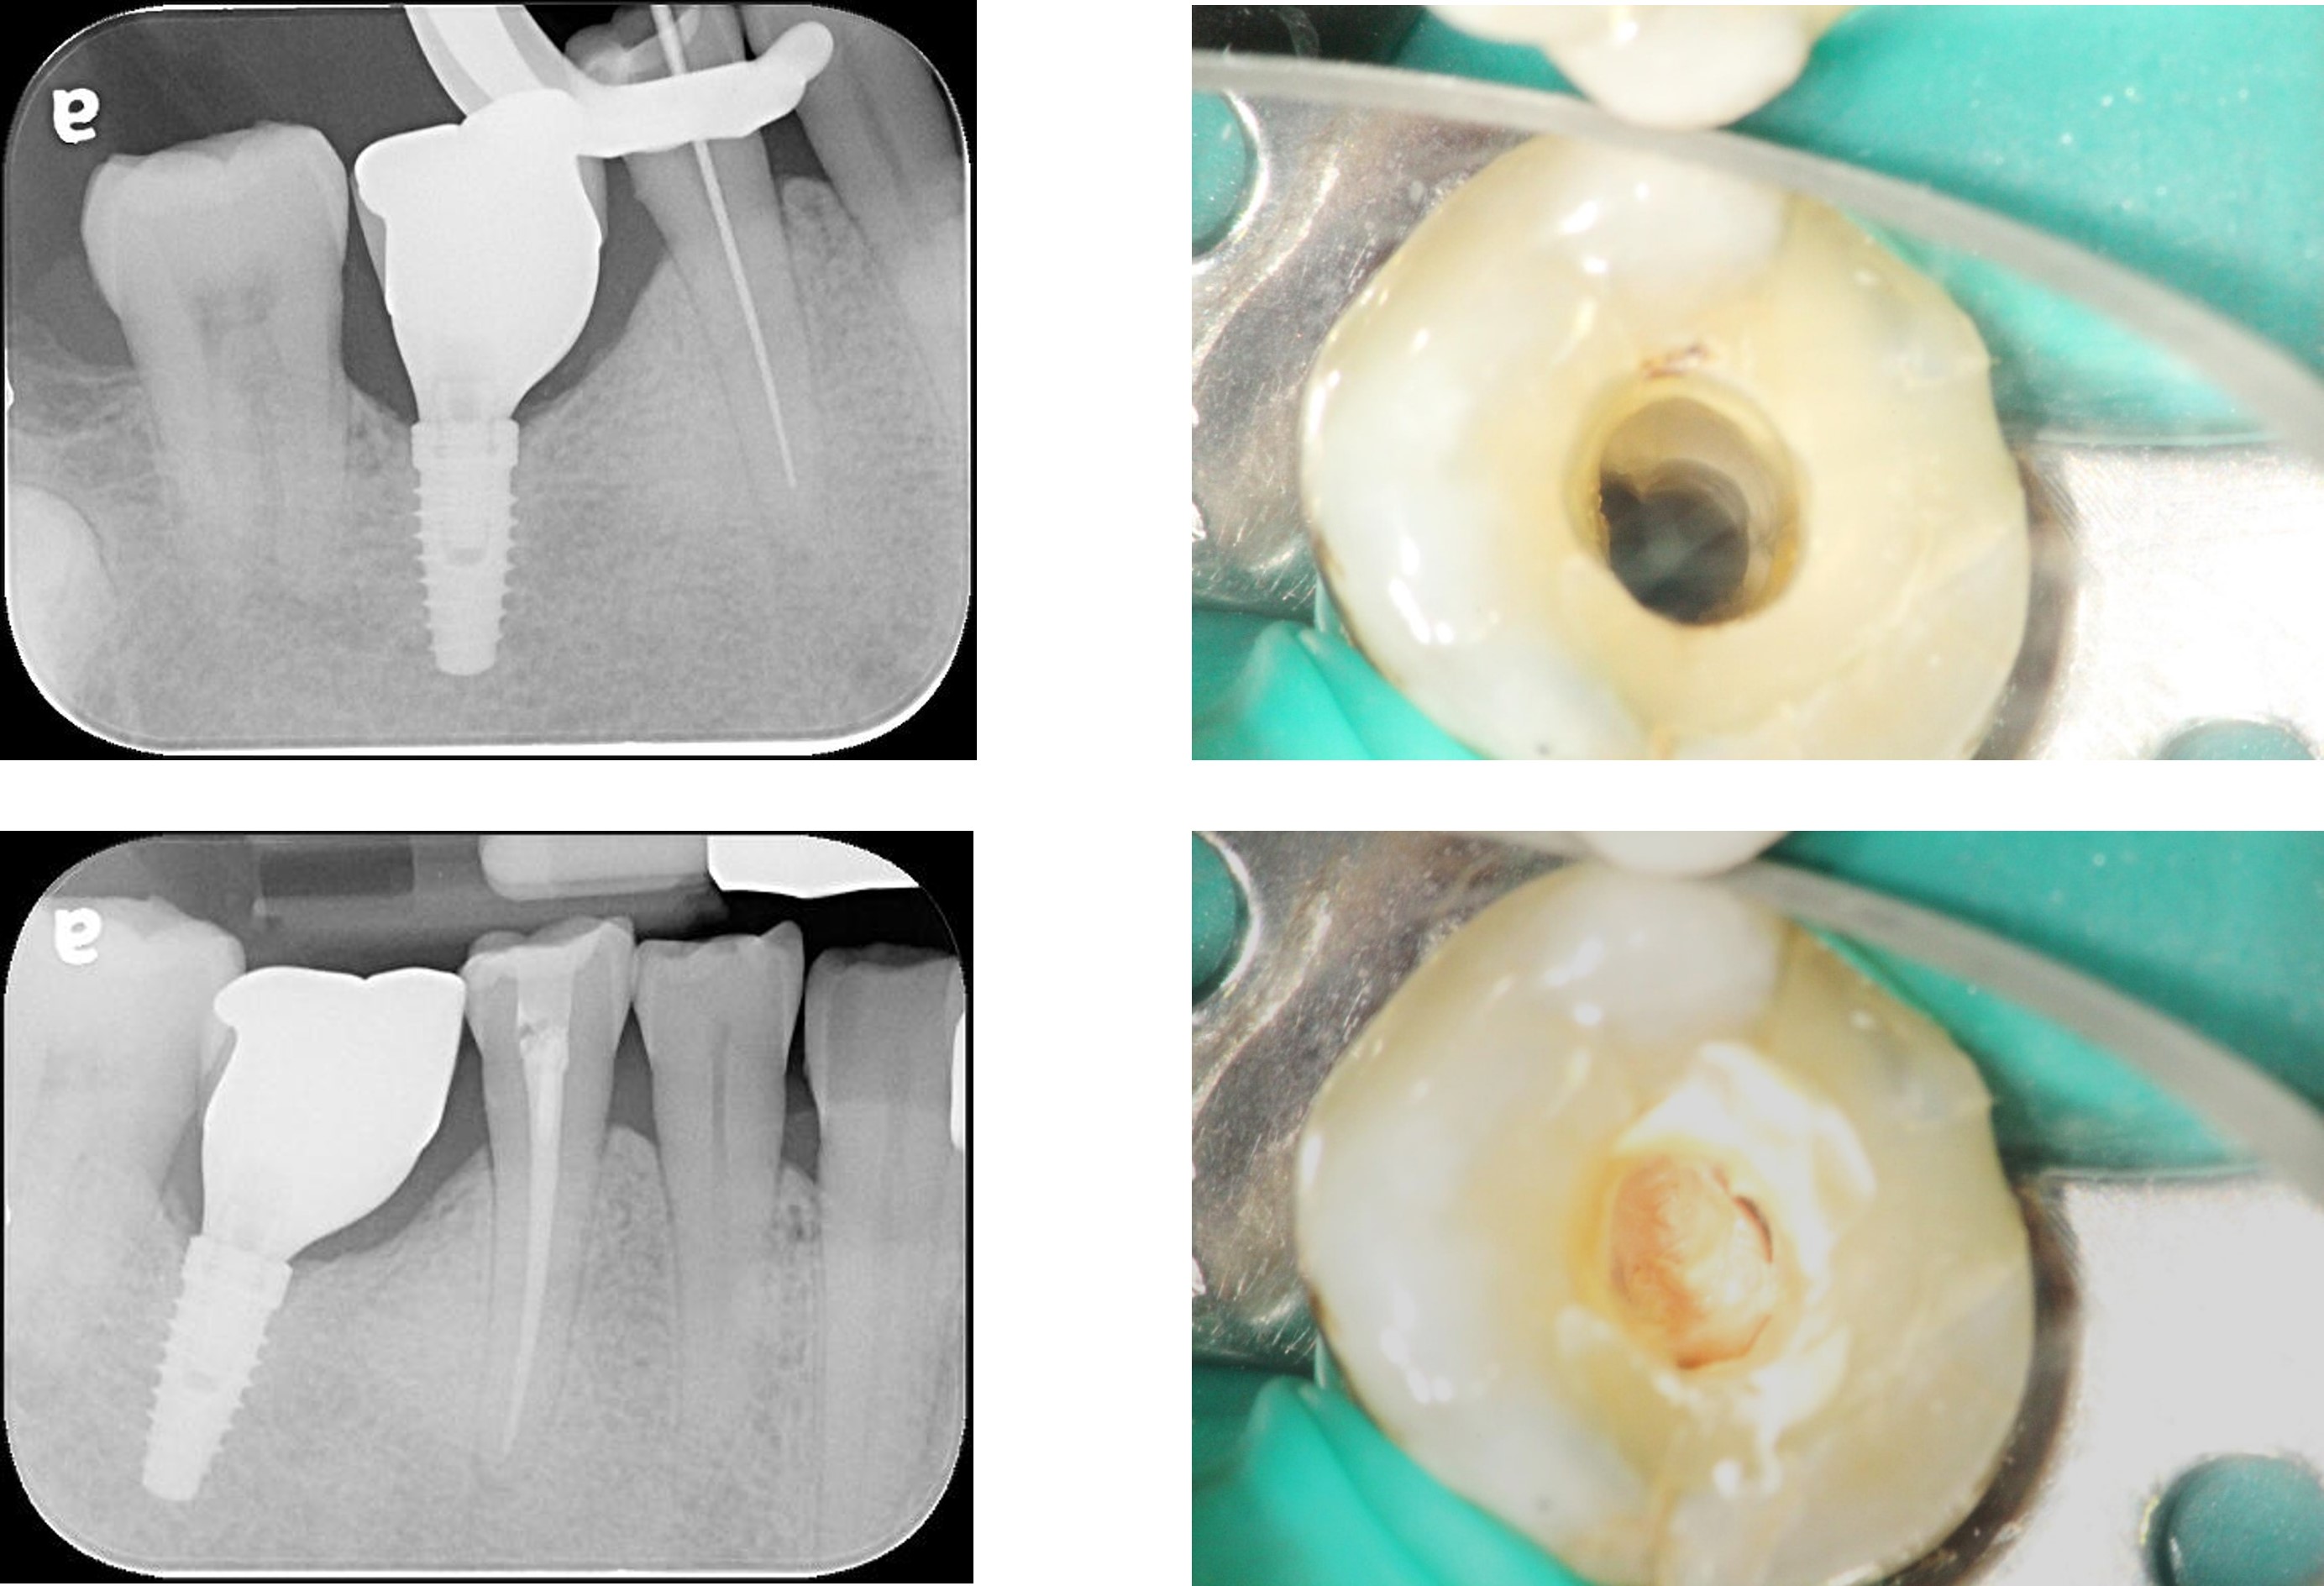

半調節咬合器上製作膺復物

咬合器上製作製作固定膺復物